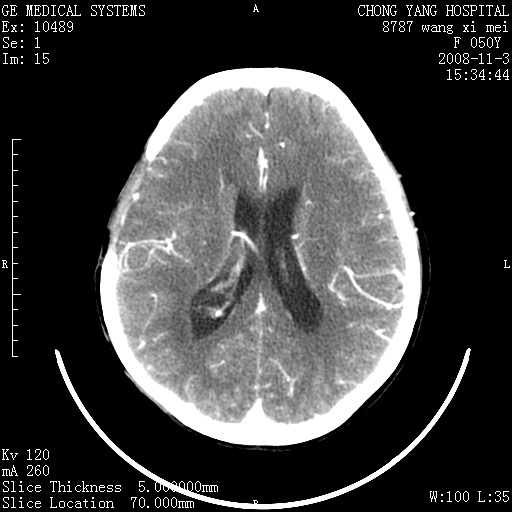

右侧颞顶部可见低密度实变影,内见不规则钙化灶,边界不清,占位效应明显,侧脑室后角受压移位,符合胶质瘤术后复发改变。

右颞骨局限性缺如,局部脑组织无外隆。右颞叶可见片状脑脊液样低密度影,边缘较清,右侧侧脑室三角区可见一块状等密度影,且伴有强化,余未见明显异常改变。

考虑:右大脑术后改变伴肿瘤复发。

手术后局部片状低密度改变(软化灶),其后方颞叶似等密度病灶,界限不清,内见钙化,有轻度占位效应,但增强后强化之血管走行如常。应不考虑:复发!

右侧颞顶部混杂密度影,内有钙化,有占位效应。应该是复发灶。结合术后片更好。

局部软化灶并钙化;无花边样强化,不象复发